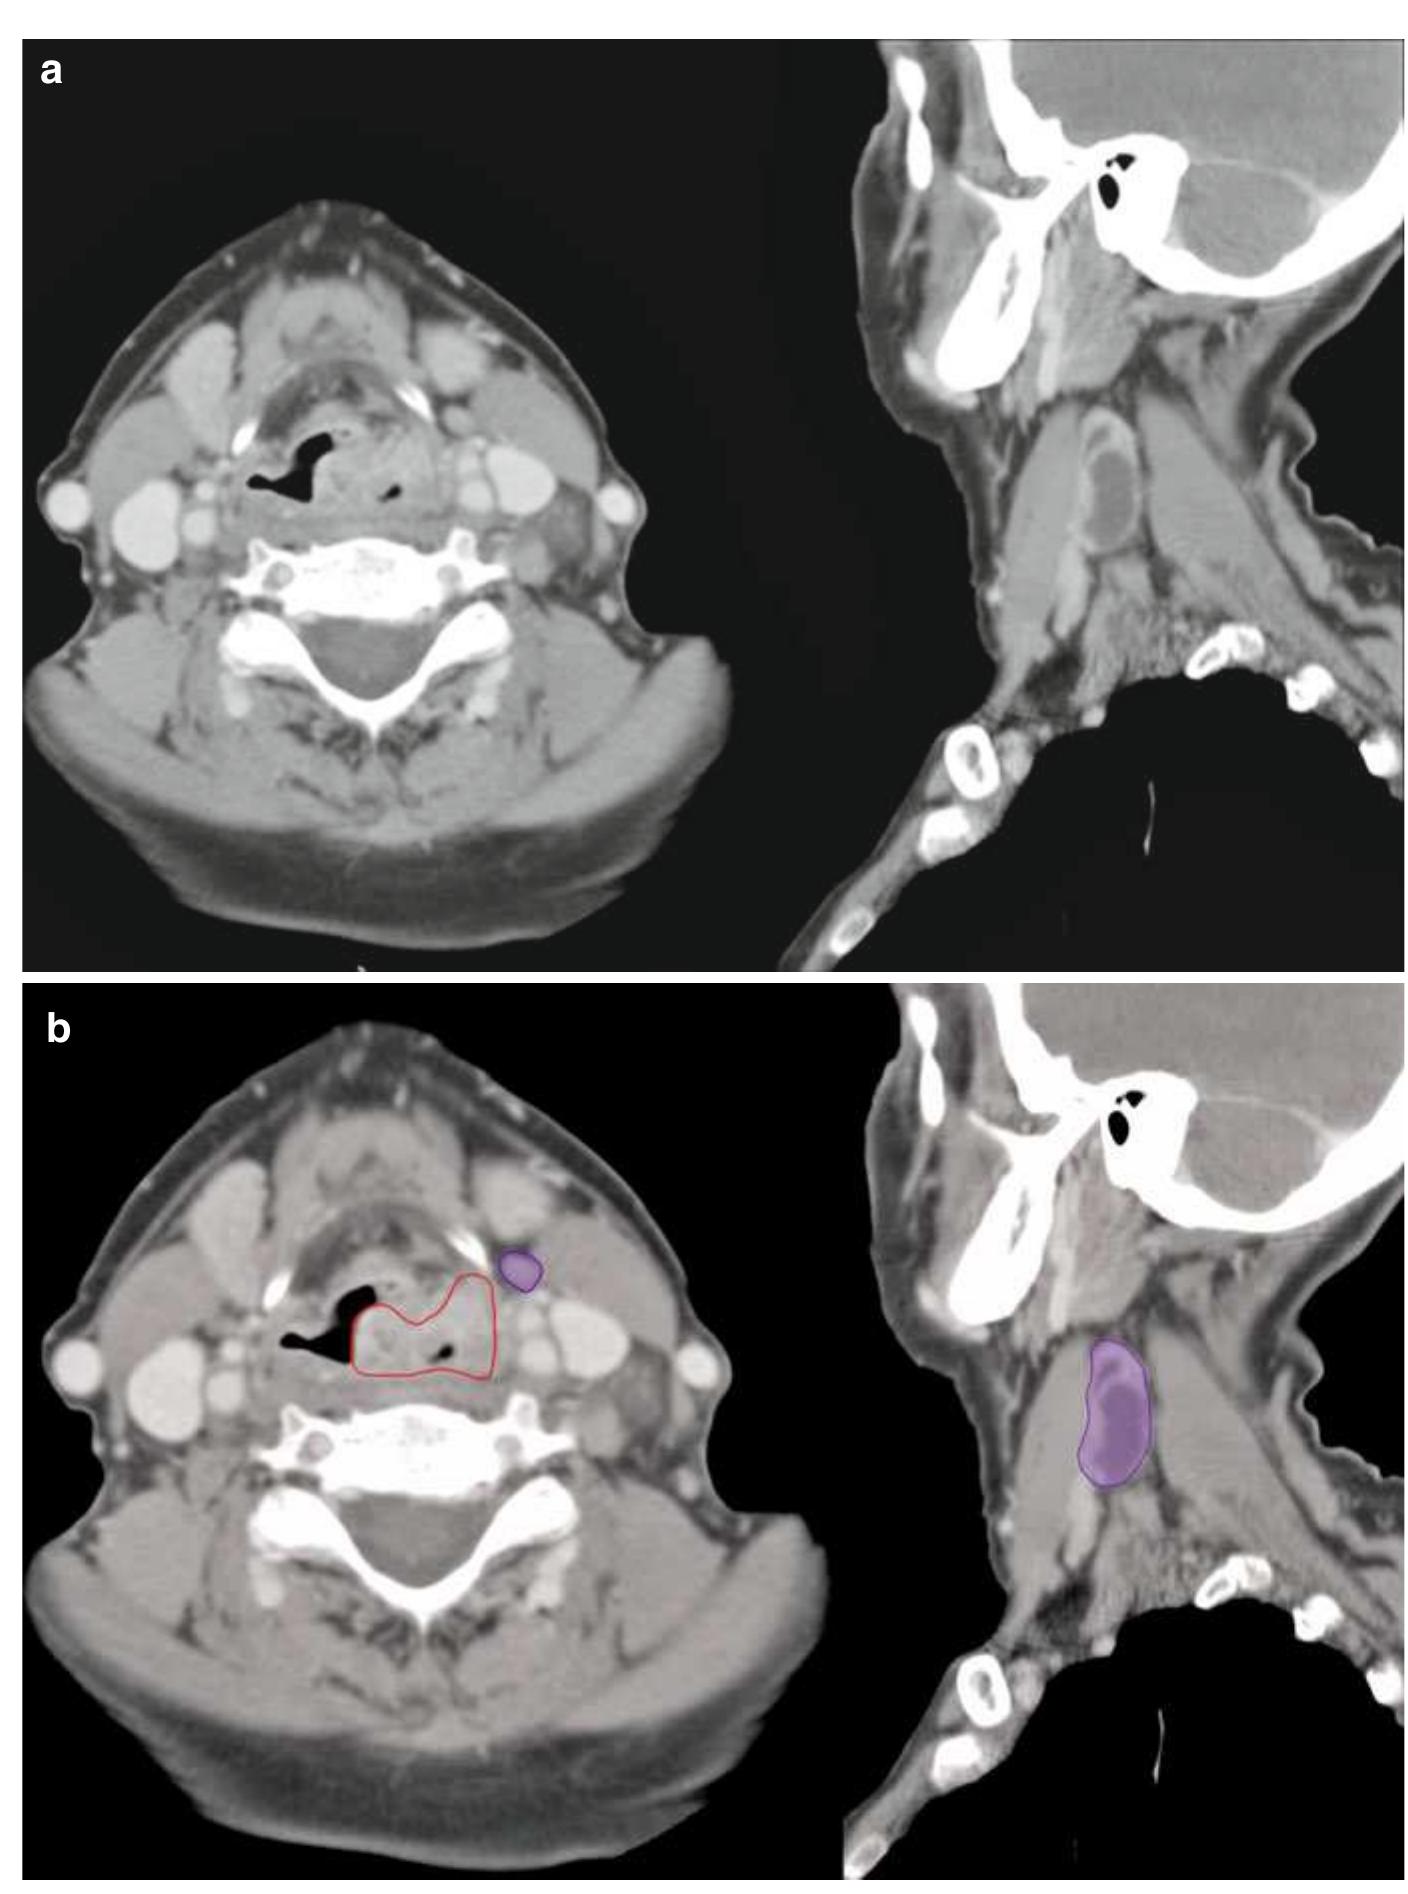

Метастаз Шеи Фото

Метастаз Шеи Фото 113 фотографий